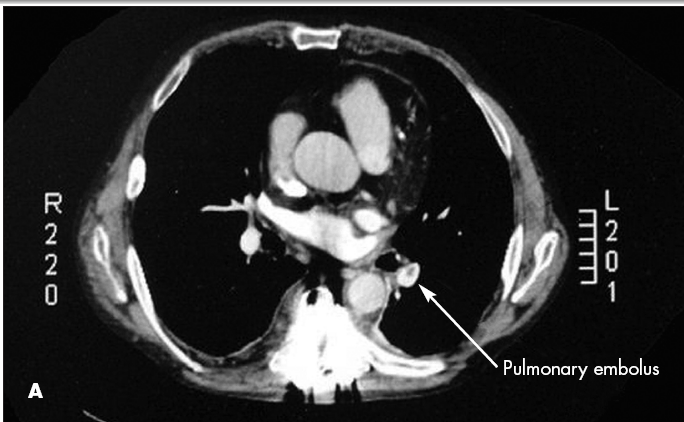

CT scans showed both a pulmonary embolus (A) and a thrombus in the wall of the abdominal aorta (B). Anticoagulation therapy was initiated. A Doppler study showed a left lower extremity deep venous thrombus. Further evaluation with transesophageal echocardiography showed a patent foramen ovale (C) and an interatrial aneurysm, with a positive bubble study.* The patient had no known history of either condition. Because of the patent foramen ovale, thrombi had traveled not only to the lungs but also to the aorta. This likely caused the spinal ischemia and paraparesis.